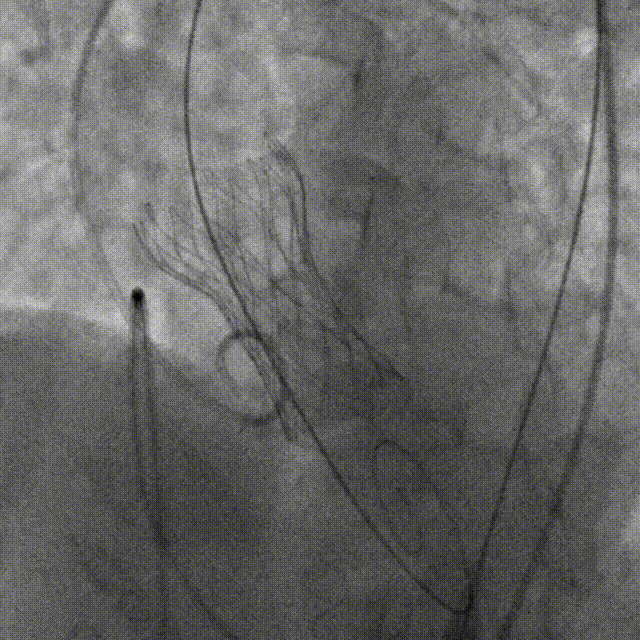

陶主任对人工瓣膜进行部分回收后再定位

瓣膜成功释放

术后即刻超声显示:无主动脉瓣返流、无瓣周漏,PGmean:8mmHg,Vmax:2m/s,LVEF:58% 。

人工瓣膜释放后造影

术后,陶主任对TaurusElite™可回收输送器过弓性能和瓣膜释放稳定性给予了高度评价,对输送系统可通过6.2mm直径的股动脉也给予了肯定。